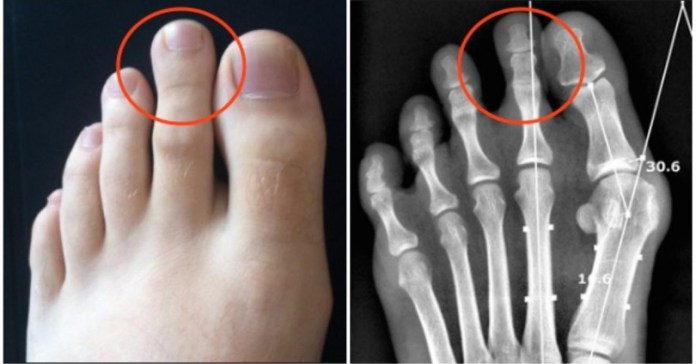

Κάποιοι το ονομάζουν “ελληνικό πόδι.” Είναι σημάδι δύναμης, εξυπνάδας και ελκυστικότητας. Δείτε πώς φαίνεται σε ακτινογραφία:

Οι περισσότεροι πιστεύουν πως η διαφορά είναι μόνο οπτική, αλλά ίσως θα ήταν χρήσιμο να παρατηρούσαμε περισσότερο τα πόδια μας, γιατί αυτό θα μπορούσε να οδηγήσει γρήγορα σε πόνους.

Όταν περπατάτε ή τρέχετε, τα πόδια κουβαλάνε το βάρος μας. Όσοι έχουν το “ελληνικό πόδι” μπορούν εύκολα να αναπτύξουν πόνο στο δεύτερο δάχτυλο, γιατί συχνά λυγίζει. Αυτό μπορεί να προκαλέσει φλεγμονή στην άρθρωση και μερικές φορές είναι πολύ επίπονο. Ο κίνδυνος είναι αυξημένος για δρομείς.